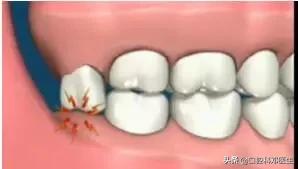

3 局部清洁死角引发龋齿

智齿萌出位置不正,即使没有顶坏邻牙,也可能与邻牙形成间隙,产生局部的“卫生死角”,食物残渣和细菌堆积在这些部位,我们日常刷牙很难清洁到,久而久之就容易引发龋齿

卫生死角